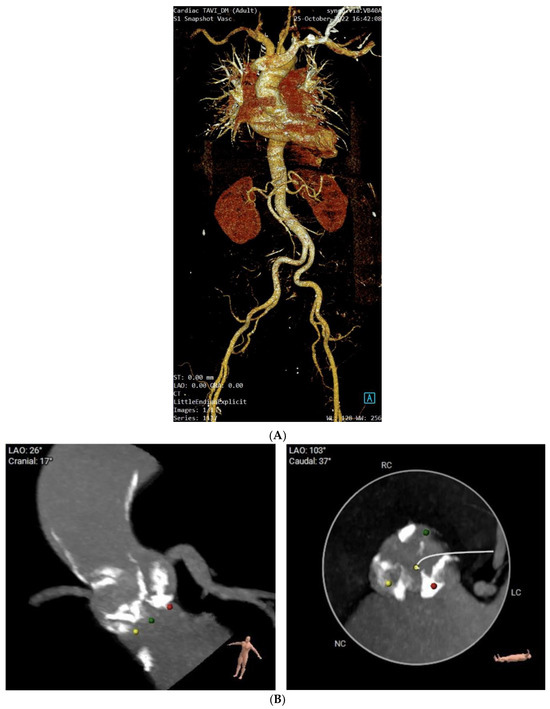

2. Case Presentation

4. Patient Management